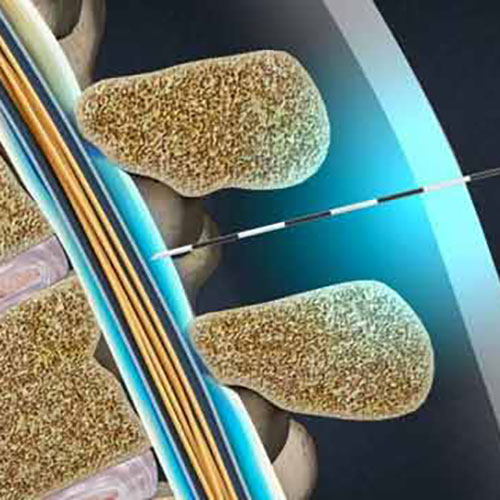

بیماری دیسک کمر

دیسک کمر دلیل شایع بسیاری از دردهای حاد، مزمن و دردهای عود کننده ی کمر و پا می باشد. معمولا بیشترین آسیب ها در دیسکهای L4-L5 یا L5-S1 ایجاد می شود ولی گاهی ممکن است در دیسک های بالاتر کمری نیز مشکل وجود داشته باشد. درد ممکن است در پائین کمر، باسن، لگن و پاها احساس شود.